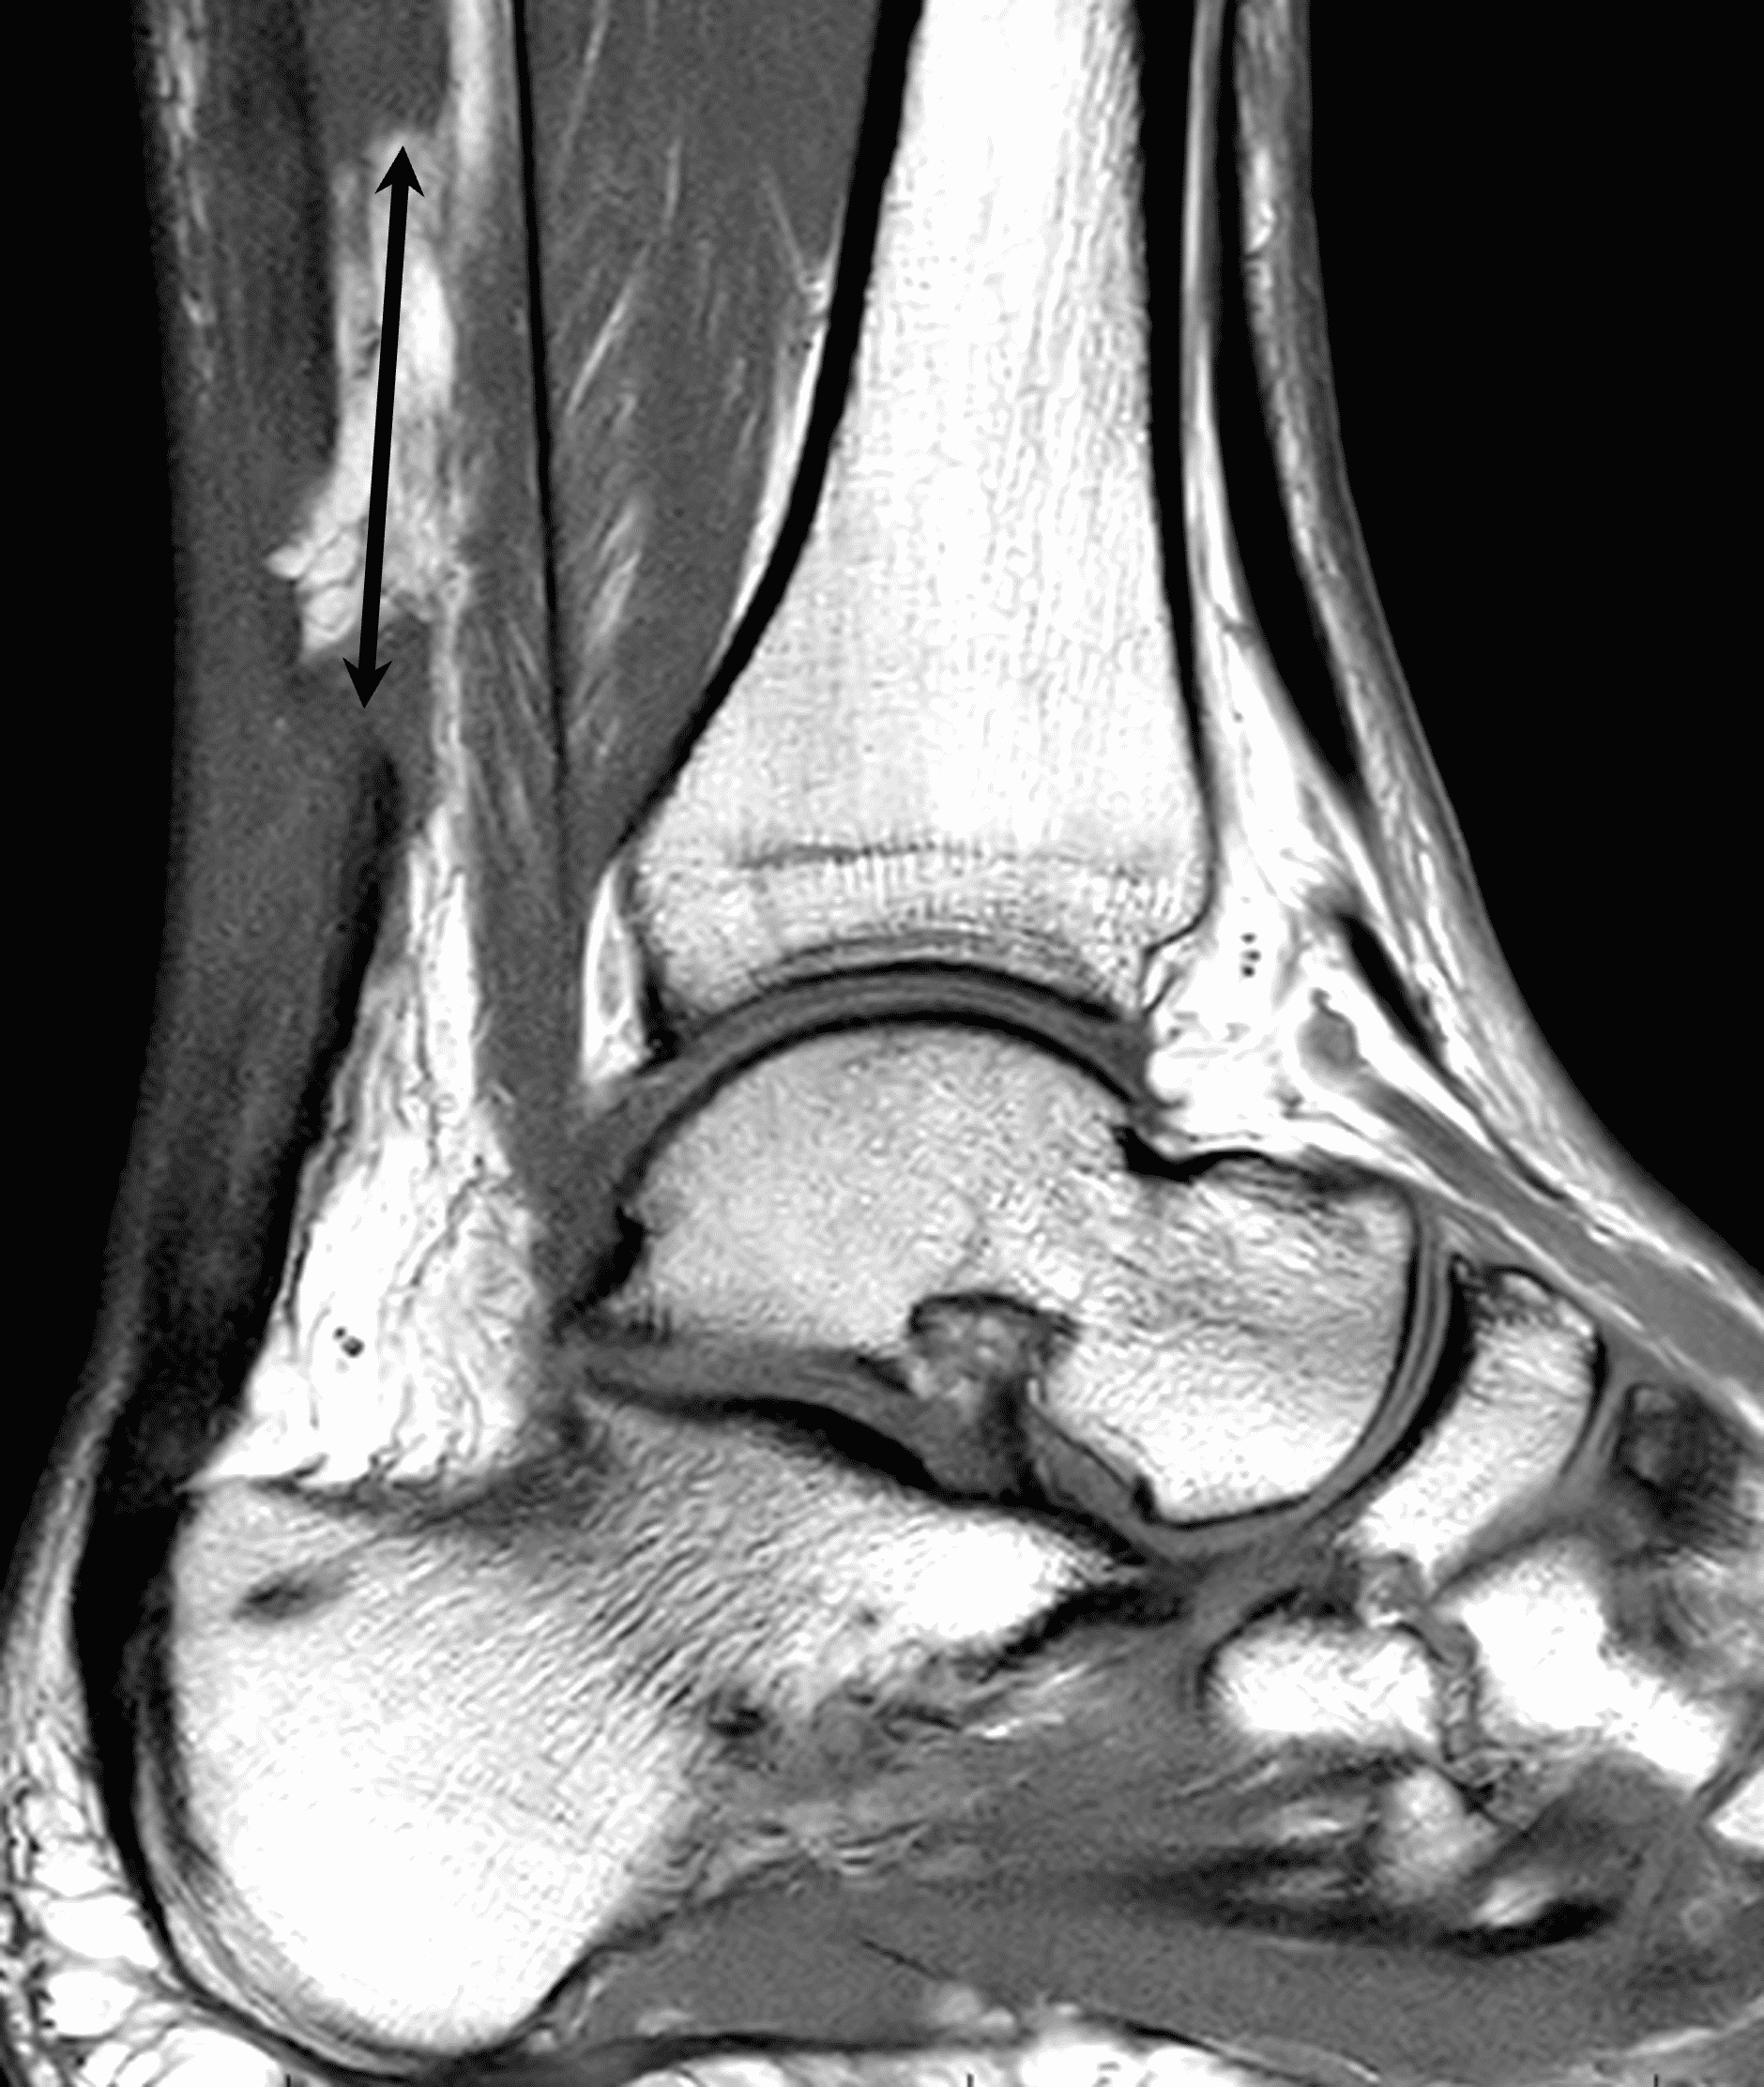

A 22 year-old male college football player presents with a “pop” and pain posterior to the right ankle during practice 1 week prior. He is unable to bear weight. Lateral radiograph (1A), sagittal fat-suppressed T2-weighted (1B), sagittal T1-weighted (1C), and transverse fat-suppressed T2-weighted images are provided. What is your diagnosis? What MRI findings affect clinical management decisions?

Figure 2: Complete Achilles tendon rupture. (2A) The lateral radiograph shows a thick and indistinct proximal Achilles tendon contour (arrows). (2B) A fat-suppressed T2-weighted image shows complete rupture of the tendon with a fluid-filled gap (yellow arrow) measuring 1.5 cm in length, located 10 cm cranial to the tendon insertion (blue arrow) and just distal to the edematous myotendinous junction (red arrow). The tear is superimposed on diffuse tendinosis. (2C) A sagittal T1-weighted image confirms the diffuse tendinosis. Fluid extends anteriorly into Kager’s fat pad (arrow) suggesting disruption of the anterior paratenon. (2D) A transverse fat-suppressed T2-weighted image through the proximal tendon shows no intact fibers (arrow), confirming the full-thickness rupture.

Acute, complete Achilles tendon rupture just distal to the myotendinous junction, superimposed on diffuse tendinosis.